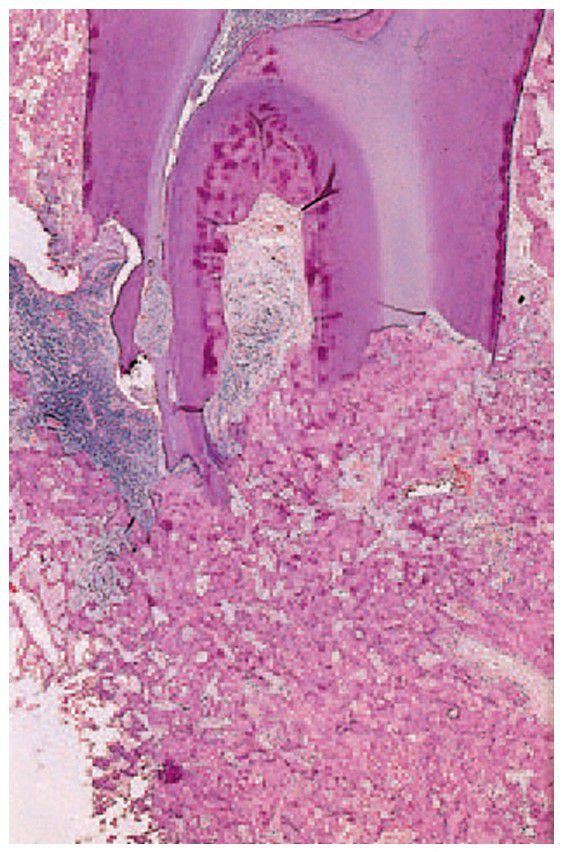

Cementoblastoma

. A dense mass of interconnected trabeculae of osteoid is fused to the resorbed roots of the fi rst permanent molar.